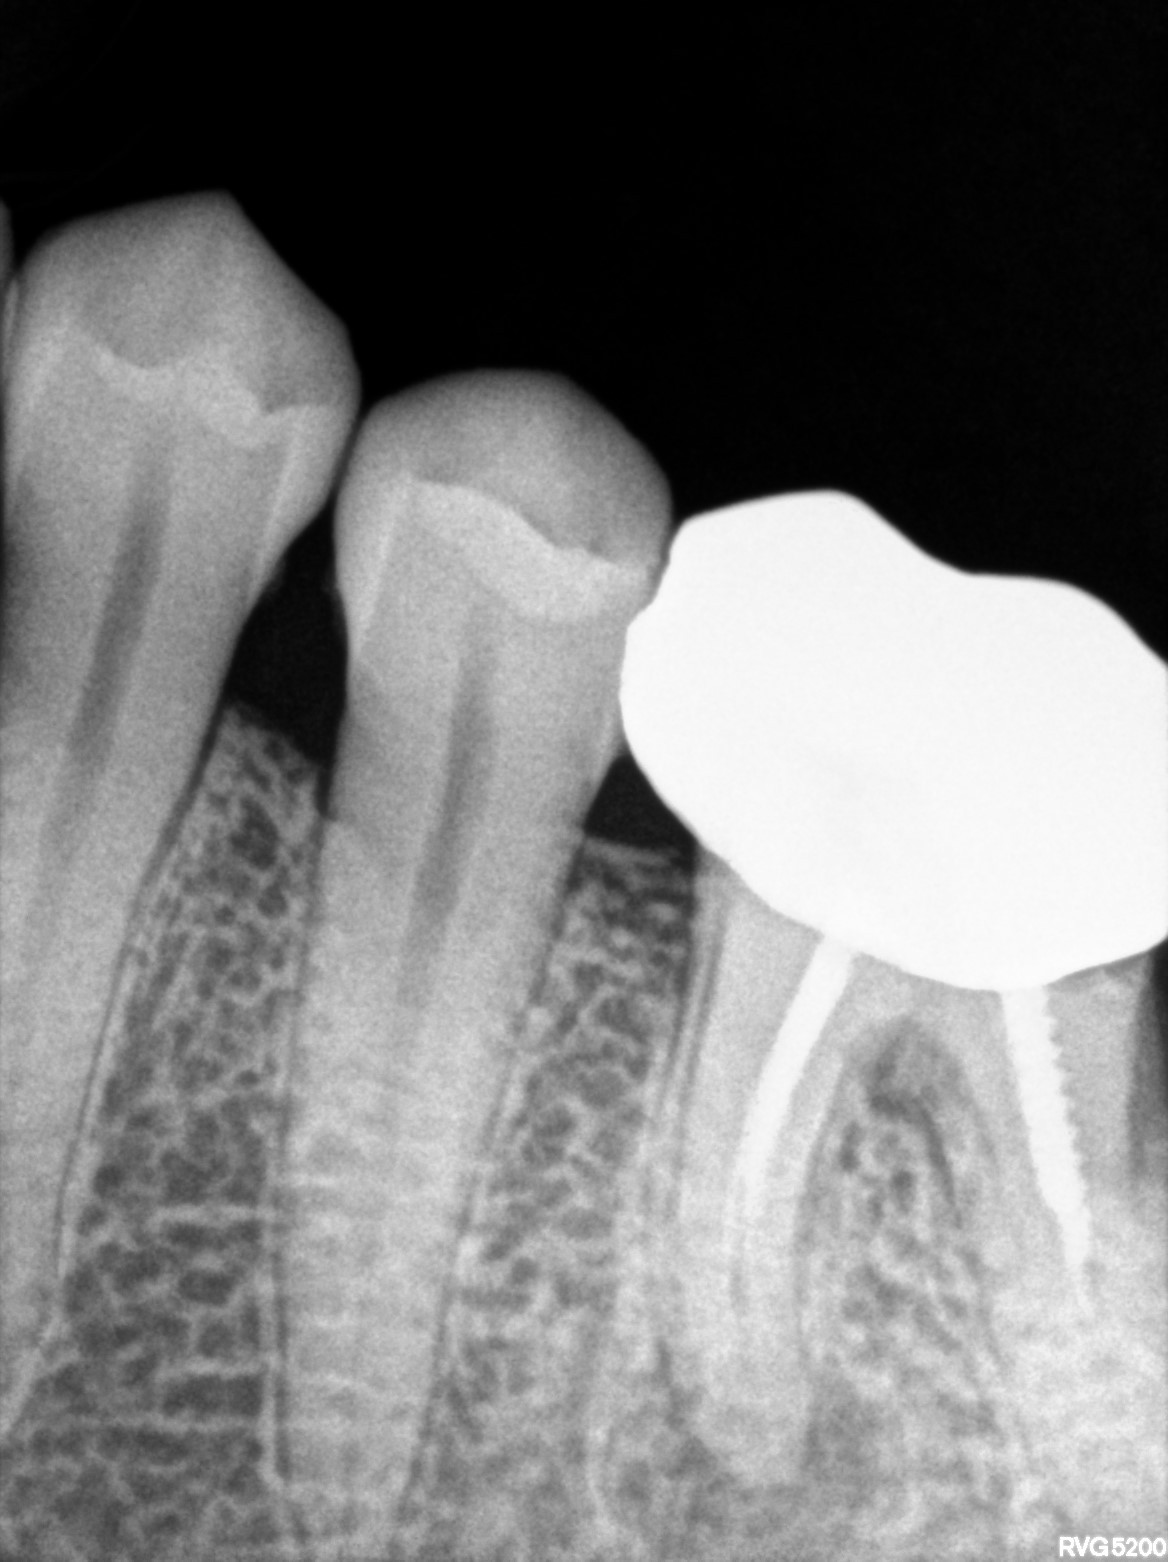

Dental Radiographs FHIR: DocumentReference · LOINC 24641-7

R56 (2).jpg

24641-7